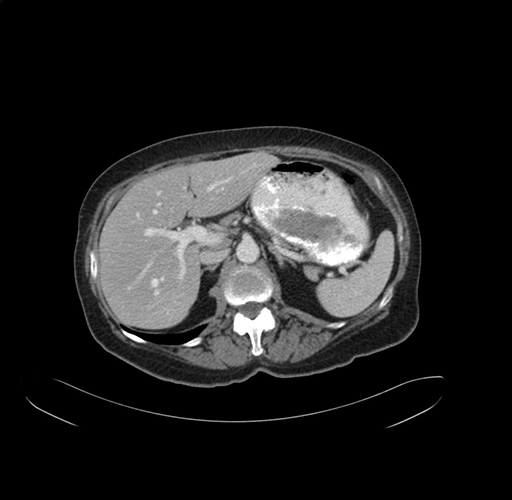

Axial Venous